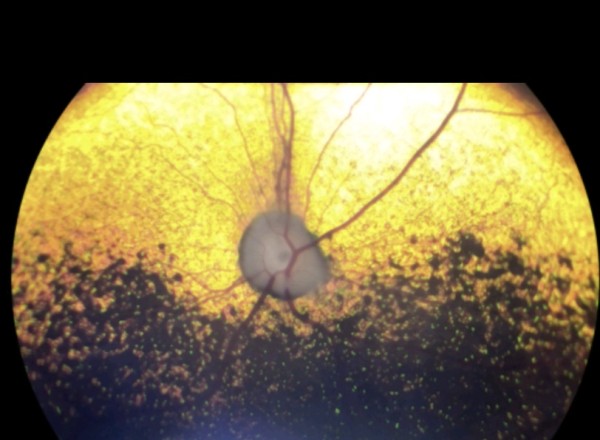

• Ophtalmoscopie directe ou indirecte : examen de la rétine, du nerf optique et du fond d’œil

• Échographie oculaire (si l’œil est opaque ou non visuel)

Ophtalmoscopie directe et indirecte. Examen lampe a fente. Examen du fond d’œil. Tonométrie. Échographie oculaire